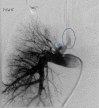

Bronchopulmonary arterial fistula consists of an abnormal connection between the bronchus and the vascular tree and is a rare but serious complication associated with a variety of lung interventions. We present a case of a 61-year-old female with a history of metastatic breast cancer treated with lumpectomy and radiation 20 years prior, who was found to have a fistula between the right pulmonary artery and the right mainstem bronchus. Our patient was treated endovascularly with coil embolization in the setting of massive hemoptysis flooding the trachea, which was successful in controlling the acute bleed, although care was withdrawn in the following days following a discussion with the family given the presence of advanced metastatic disease. This case illustrates the use of endovascular techniques to treat an actively bleeding bronchopulmonary arterial fistulae, including a review of the existing literature regarding the optimal endovascular management strategy. Although our patient did not achieve the best outcome, endovascular intervention with stent-placement or embolization can serve to temporarily halt blood flow through the fistula, stabilizing the patient and allowing for more radical therapy after improvement.